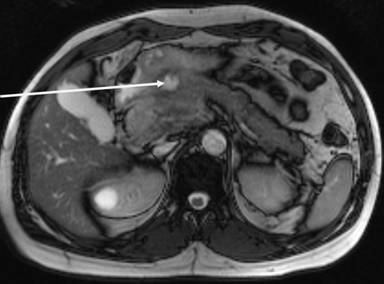

He came to the emergency room because he had felt abdominal pain in the epigastric area for two months, but the pain became constant and with increased intensity. He reported nausea and vomiting, but no modification of bowel habits. Clinical examination revealed stable hemodynamic signs but a marked tenderness with focalized guarding in the right hypochondrium and epigastric region. Laboratory analysis did not reveal anything specific, except elevated lipases at 696 U/L (reference range : 114-286 U/L). Abdominopelvic computed tomography (CT) (Figure 1) and then magnetic resonance imaging (MRI) showed kissing gastric ulcers of the antrum, with the posterior ulcus perforating the gastric wall into pancreatic parenchyma and a Balthazar C associated pancreatitis (Figures 2 and 3). Imaging also disclosed a left portal branch thrombosis and a portal biliopathy (with an amount of thin veins around the main biliary duct) (Figure 4). First, evolution was satisfactory with medical treatment (fasting, gastric protectors, and nasogastric tube). But pain returned with every attempt of food intake. Finally, an endoprosthesis in the pancreatic main duct was placed with a positive result and symptom resolution.

Figure 3. MRI showing a posterior lesion penetrating into the pancreas (arrow). |

Our patient presented a kissing ulcer, with anterior and posterior lesions, the second one perforated into pancreatic parenchyma, being the suspected cause of acute pancreatitis. We ruled out an acute ethylic intoxication and biliary pancreatitis.